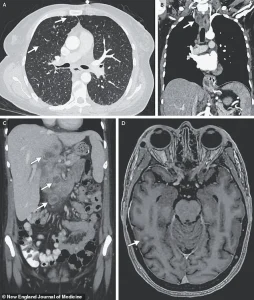

X-ray scans conducted during her stay uncovered small nodules in her lungs, a finding suggestive of bacterial infection.

Further imaging revealed lesions in multiple organs, including the liver, lymph nodes, pancreas, and brain—indications of a systemic infection.

After nine weeks of testing, including biopsies and bacterial cultures, doctors confirmed the presence of *Mycobacterium tuberculosis*, the pathogen responsible for tuberculosis (TB).

This diagnosis marked a rare but severe case of disseminated TB, a form of the disease that spreads beyond the lungs to affect multiple organs.

The severity of her condition was underscored by the fact that the TB had reached her brain, a rare but particularly dangerous complication.

If left untreated, the infection can progress to severe respiratory failure, extensive lung damage, and even the spread of bacteria to other organs, such as the brain, liver, and pancreas.

In advanced cases, TB can cause paralysis, strokes, and other neurological complications due to increased intracranial pressure and damage to vital tissues.